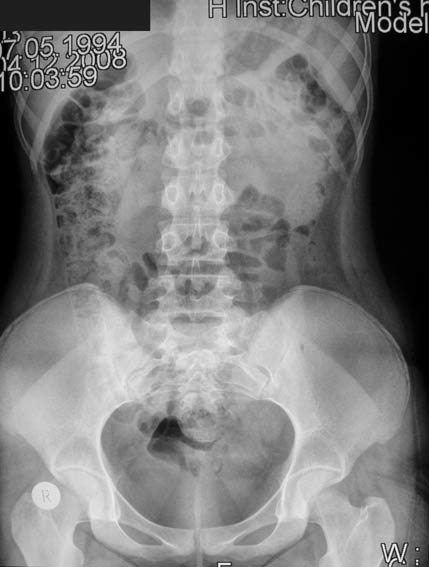

Камень н\3 левого мочеточника, девочка 14 лет

Неделю назад Был приступ болей в пояснице слева, тошнота, рвота. Приступы повторялись ежедневно. Микрогематурия.